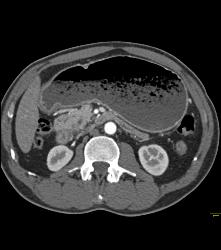

Antral Carcinoma- See Sequence